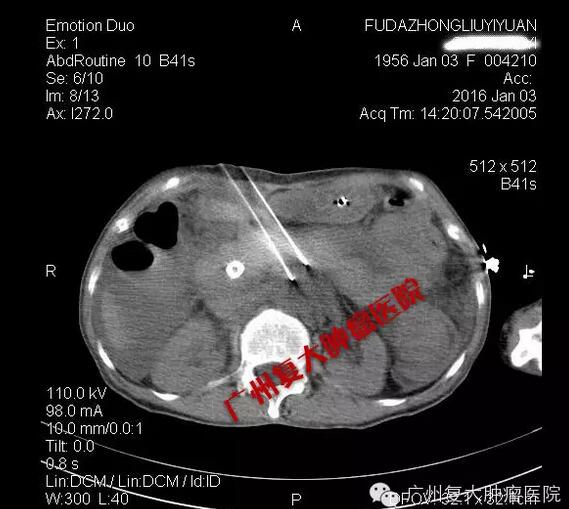

患者的CT检查结果

纳米刀消融肿瘤

陈女士的手术很顺利,CT加B超双引导双监测,肿瘤消融达到了90%以上。目前患者已经顺利脱离呼吸机,病情平稳,今天已离开ICU回到普通病房。我们计划几天后开始给予其他的抗肿瘤治疗,包括微血管介入和肿瘤免疫治疗。希望通过我们的努力,能给这位晚期胰腺癌患者更多的生存机会。祝福她!